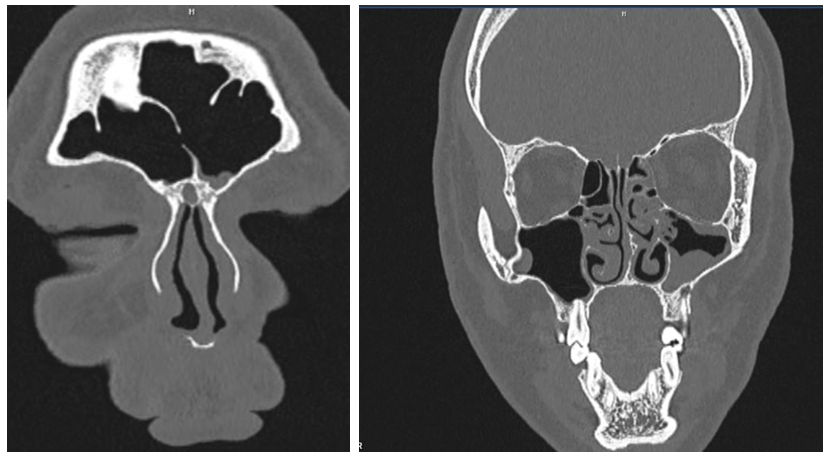

Analysis of CT images in the main patient group revealed characteristic radiologic features for each disease subgroup.In patients with frontal sinusitis (n = 37), tomograms demonstrated diffuse or partial reduction in the pneumatization of the frontal sinuses with homogeneous or loculated opacification corresponding to the accumulation of mucopurulent content (Fig. 2). In some patients, mucosal thickening up to 6–8 mm was observed, involving the frontonasal duct. In certain cases, expansion and deformation of the anterior sinus wall, as well as signs of a subperiosteal abscess, were visualized. | Figure 2. MSCT – findings consistent with left-sided frontal sinusitis. Frontal sinuses – mucosal thickening at the floor of the left frontal sinus measuring 0.4–0.7 cm, +10 to +12 HU |

In patients with maxillary sinusitis (n = 42), the most common finding was complete or subtotal opacification of the maxillary sinus with fluid levels, mucosal hyperplasia, and obliteration of the natural ostium. In some cases, thickening of the bony sinus walls (sclerosis) and involvement of adjacent structures — the ethmoidal labyrinth and the inferior nasal turbinate — were noted. In certain patients, polypoid growths filling the sinus lumen were identified.In patients with ethmoiditis (n = 45), the anterior and/or posterior cells of the ethmoidal labyrinth exhibited diffuse mucosal thickening alternating with cell-like lucencies, a pattern consistent with inflammatory involvement of the sinus walls. In acute cases, the ethmoidal cells were completely filled with pathological content of soft-tissue density, often accompanied by obstruction of the adjacent drainage pathways (Fig. 3). In chronic cases, signs of mucosal hyperplasia and polypoid growths were evident, sometimes leading to partial remodeling of the bony cell walls. The process was frequently associated with concurrent involvement of the maxillary or frontal sinuses, which may complicate the clinical presentation and contribute to persistent or recurrent disease. In several cases, subtle osteitic changes and thickening of the lamina papyracea were noted, potentially increasing the risk of orbital complications in advanced stages. | Figure 3. MSCT – findings consistent with ethmoiditis. Ethmoidal sinuses – pathological contents in the cells with a density of +4 to +10 HU |

CT data from all patients were utilized not only for clinical diagnostic purposes but also to compile a comprehensive dataset of images that served as the basis for training and testing artificial intelligence algorithms. The integration of a deep learning–based system into the CT image analysis workflow for the main study group demonstrated the model’s ability to accurately detect and localize key radiologic features characteristic of each type of paranasal sinus pathology. This approach contributed to an improvement in diagnostic accuracy, reproducibility, and standardization of interpretation, while reducing the influence of subjective factors.• Frontal sinusitis (n = 36) — The AI system consistently recognized hypodense filling zones within the frontal sinuses, corresponding to mucopurulent accumulation, along with areas of mucosal thickening and obliteration of the frontonasal duct. Automatic segmentation provided clear boundaries between pathological content and normally aerated sinus cavities, ensuring precise volumetric assessment. The algorithm demonstrated particular sensitivity in detecting minimal hyperplastic changes that might be overlooked during routine visual analysis by a radiologist. Additionally, the system generated high-quality multiplanar reconstructions, allowing improved visualization of the extent of involvement and potential obstruction of drainage pathways.• Maxillary sinusitis (n = 42) — The AI algorithm showed strong performance in identifying characteristic features such as horizontal fluid levels, diffuse mucosal hyperplasia, and sclerosis of the bony sinus walls. In cases of polypoid changes, the system accurately segmented the masses, provided volumetric measurements, and differentiated them from retained secretions or mucosal thickening. Furthermore, the AI reliably detected contiguous involvement of the ethmoidal labyrinth, thereby enabling a more comprehensive evaluation of disease spread. By flagging these areas automatically, the algorithm facilitated more consistent reporting and reduced the likelihood of underestimating the inflammatory process.• Ethmoiditis (n = 45) — The AI system effectively identified diffuse mucosal thickening within the anterior and/or posterior cells of the ethmoidal labyrinth, accurately differentiating it from normal mucosal folds or minor anatomical variations. In acute cases, the algorithm recognized complete soft-tissue opacification of ethmoidal cells with high confidence, often associated with obstruction of adjacent drainage pathways. In chronic disease, it detected patterns of mucosal hyperplasia and polypoid tissue proliferation, providing detailed segmentation and volumetric quantification of the lesions. The system also demonstrated the capability to visualize subtle bony changes, such as thickening of the lamina papyracea or remodeling of intercellular septa, which may be early indicators of osteitic involvement. Importantly, the AI model automatically highlighted cases with concomitant maxillary or frontal sinus disease, thus supporting a comprehensive assessment of the inflammatory spread.AI-assisted analysis of paranasal sinus pathologiesThe application of a deep learning–based image analysis system to CT datasets of patients with various paranasal sinus pathologies demonstrated substantial potential for enhancing diagnostic precision, standardization, and reproducibility. For each disease category — frontal sinusitis, maxillary sinusitis, and ethmoiditis — the algorithm provided accurate detection, delineation, and quantitative assessment of pathological features. It was able to identify minimal changes that might be overlooked during routine visual review, thus reducing the subjectivity inherent in human interpretation.• In frontal sinusitis, the system consistently detected hypodense filling, mucosal thickening, and frontonasal duct obstruction, delivering precise segmentation and volumetric measurements.• In maxillary sinusitis, the algorithm reliably recognized fluid levels, diffuse mucosal hyperplasia, bony sclerosis, and polypoid lesions, as well as associated ethmoidal involvement.• In ethmoiditis, the model effectively segmented diffuse thickening, opacified ethmoidal cells, hyperplastic and polypoid changes, and early bony remodeling, while flagging cases with spread to adjacent sinuses.By integrating such AI-based tools into clinical workflows, radiologists can benefit from automated, objective, and reproducible evaluations, potentially improving both diagnostic accuracy and treatment planning. The visualization of recognition results included the overlay of color-coded contours of segmented regions onto the original CT slices (Fig. 4). This allowed the physician to simultaneously evaluate both the original image and the automated annotation, as well as to correlate the AI findings with clinical data. | Figure 4. Example of visualization of automatic segmentation results of pathological changes in the paranasal sinuses on coronal CT slices: A — original image without annotation; B — overlay of color-coded contours automatically highlighting mucosal thickening (yellow), fluid levels (blue), and polypoid masses (pink) |